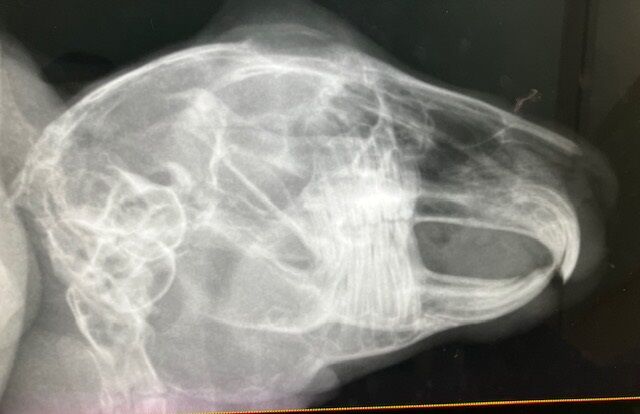

術前の血液検査、レントゲン、いずれも問題ありません。

※白血球の上昇などはストレス起因と判断できるレベル、と、

血小板は機械の誤作動による、顕微鏡で別途確認済

奥歯も問題なし。

12月4日、ドナちゃん避妊手術しました。